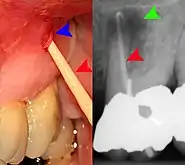

- Radiographs utilized to find dental caries and bone loss laterally or at the apex.

Decay (green) with apical abscess (blue)

Gutta-percha point indicating abscess origin